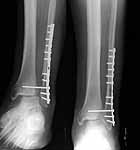

Below is a case referred to me by a fellow orthopaedic surgeon. This is a 50 y.o. gentleman s/p motorcycle accident who suffered an open ankle fracture with syndesmosis disruption. The open wound was over the medial malleolus. He was treated with I&D and ORIF. Postop xrays revealed disruption of the ankle mortise and he was taken back to the OR where a tibiotalar pin was placed after reduction of the ankle mortise. The pin was removed a few weeks later and his ankle subluxed again. He was then referred to me.

He is currently approximately 4 months out from the injury. He has no overt signs of infection and his ESR and CRP are normal. His fibula appears out to length but I believe is malrotated and his syndesmosis is malreduced. I plan to remove hardware, obtain cultures and reduce the syndesmosis and hold it with two syndesmotic screws. I also plan to open the medial side and remove any scar tissue in the ankle joint preventing reduction. I appreciate any other comments.

Has the syndesmosis ever been reduced? I don't think so. The fibula looks malreduced to me. From the pin tracks in the tibia and talus it looks like the medial clear space has always been wide. Is there something in it like posterior tibial tendon? Keep that in mind when you are "debriding" it.